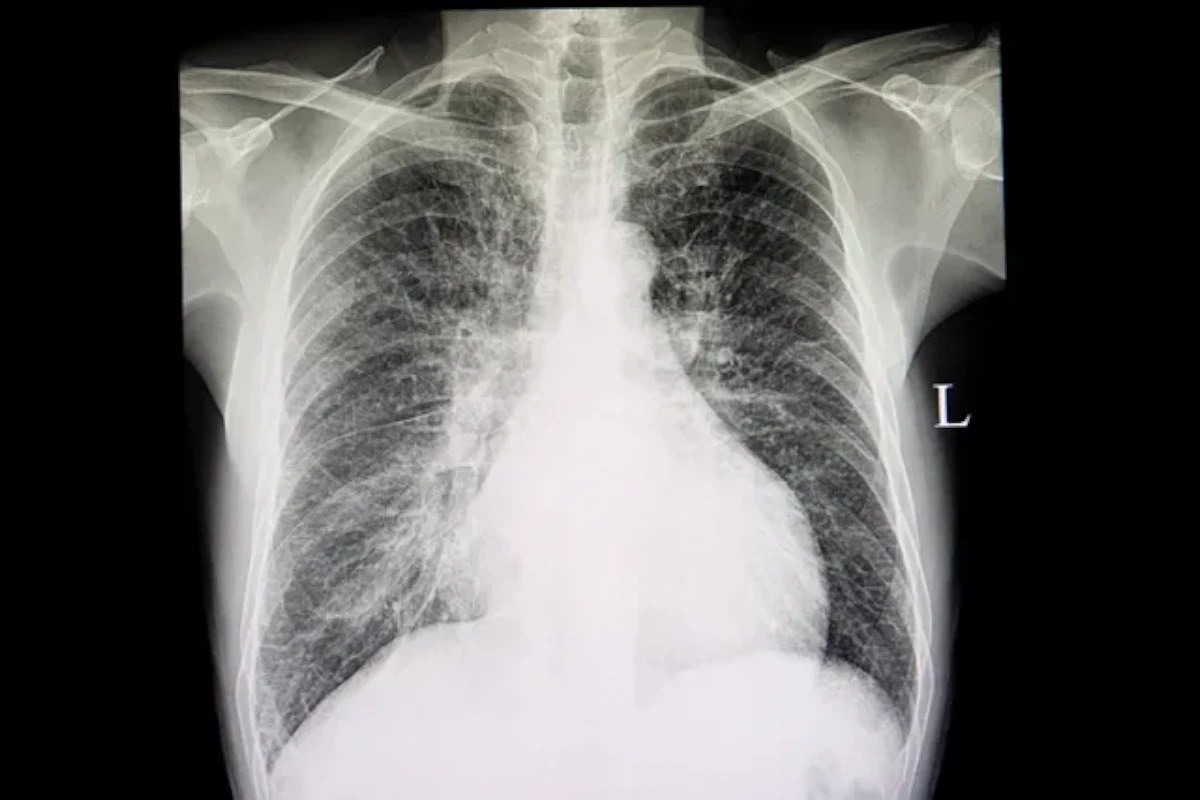

Chest X-ray